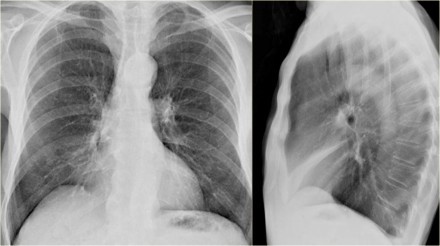

胸疾病胸片表现之肺不张

肺不张胸片表现

肺不张x线表现

肺不张胸片典型图片

肺不张胸片表现图片